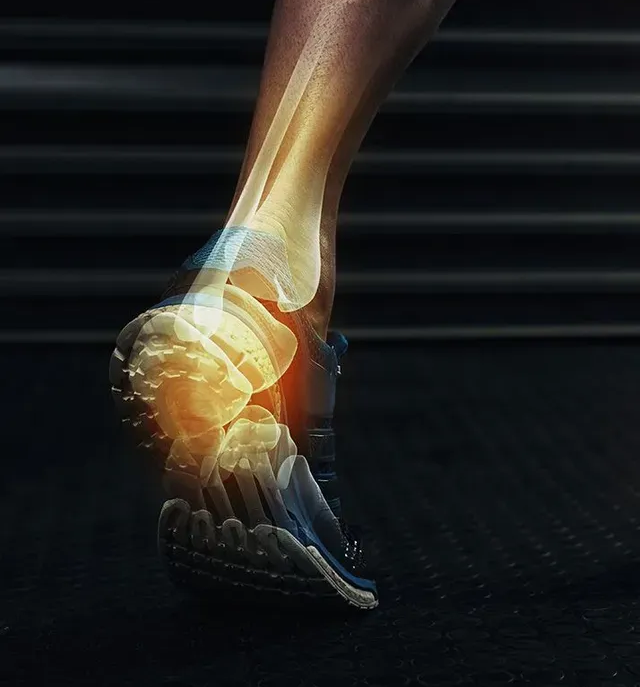

Our Foot & Ankle Services

We provide complete foot and ankle care for patients of all ages, including injury treatment, pain relief, diabetic foot management, and preventive care. Our goal is to restore comfort, mobility, and long-term health through personalized treatment plans and advanced diagnostics. Explore the services below to see how we can help you stay active and pain free.